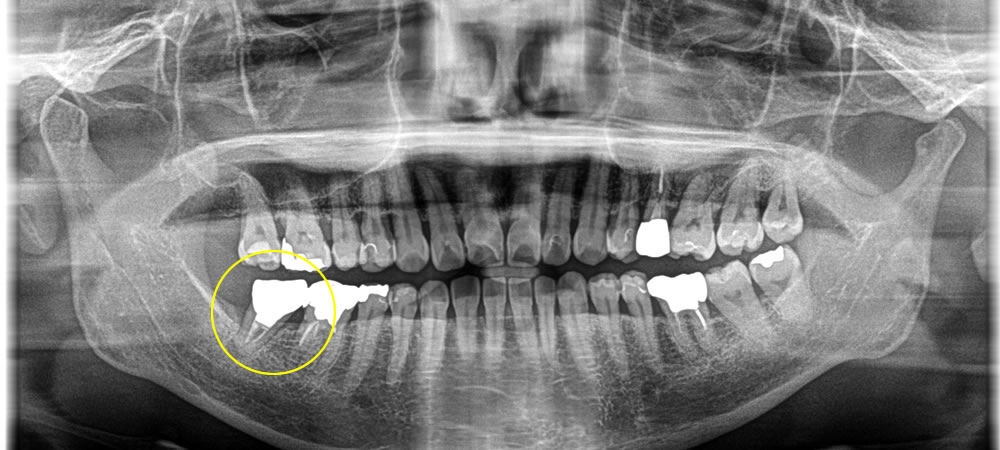

根破折で根の先端に膿がたまっているため抜歯しインプラントで修復した症例